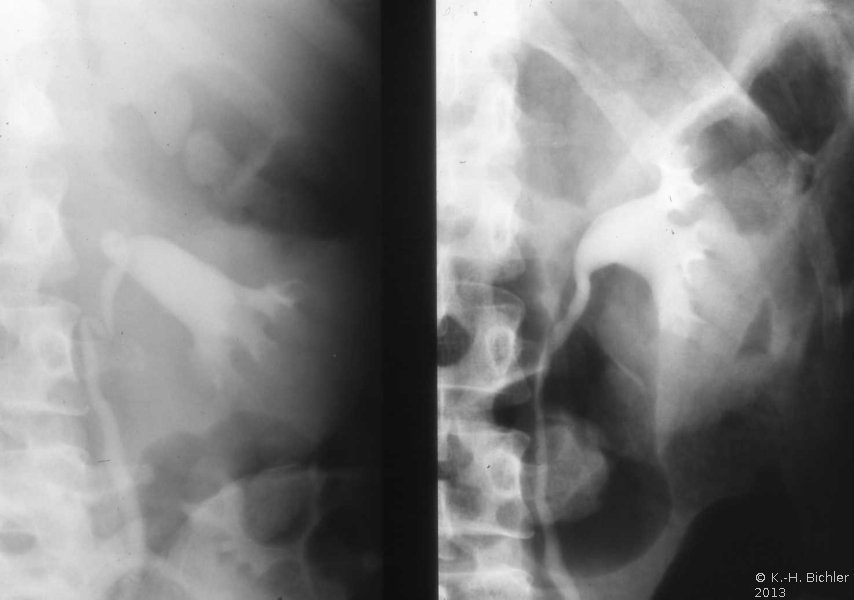

In einem weiteren Beispiel fand sich eine 8x10 cm große Nebennierenzyste, die in der Angiographie eine deutliche Abdrängung der rechten Niere zeigt